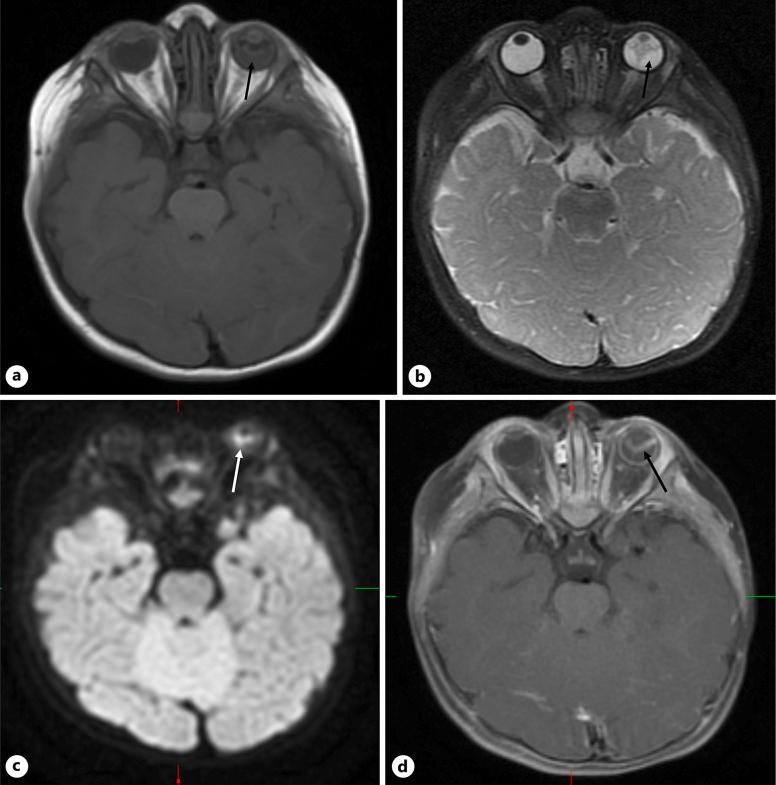

An 11-month-old female presented with poor visual behavior since birth and an intraocular mass in the left eye. Examination under anesthesia revealed a detached retina rolled into a stalk attached to the optic nerve in the right eye and a white retrolental mass with perfused vessels in the left eye. Magnetic resonance imaging demonstrated a heterogeneous mass filling the left globe with diffusion restriction and contract enhancement. Aqueous humor liquid biopsy was performed in both eyes with low DNA yield and no mutations associated with retinoblastoma were identified. The patient was observed with no interval change in examination for 6 months.

一名11个月大的女性自出生以来视力行为不佳,左眼有眼内肿物。麻醉下检查发现右眼视网膜脱离并卷成附着于视神经的蒂,左眼有一个有血管灌注的白色晶状体后肿物。磁共振成像显示一个异质性肿物充满左眼球,有弥散受限和强化。对双眼进行了房水液体活检,DNA产量低,未发现与视网膜母细胞瘤相关的突变。对该患者进行了观察,6个月内检查无间隔变化。